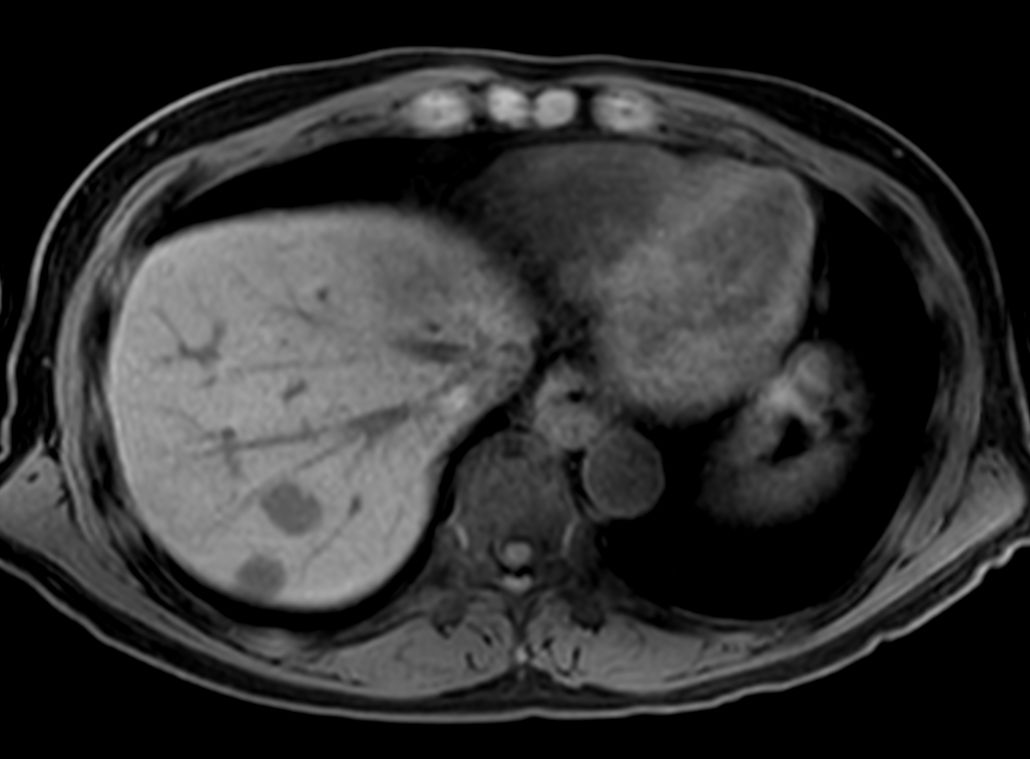

Liver metastasis – Free breathing

Patient with liver metastasis. ExamCard includes Compressed SENSE to shorten the breath hold time, VitalEye for touchless respiratory sensing, mDIXON Quant for non-invasive liver fat fraction quantification and 4D FreeBreathing to perform multi-phase contrast-enhanced MRI studies.

T2w TSE - Breath hold Compressed SENSE